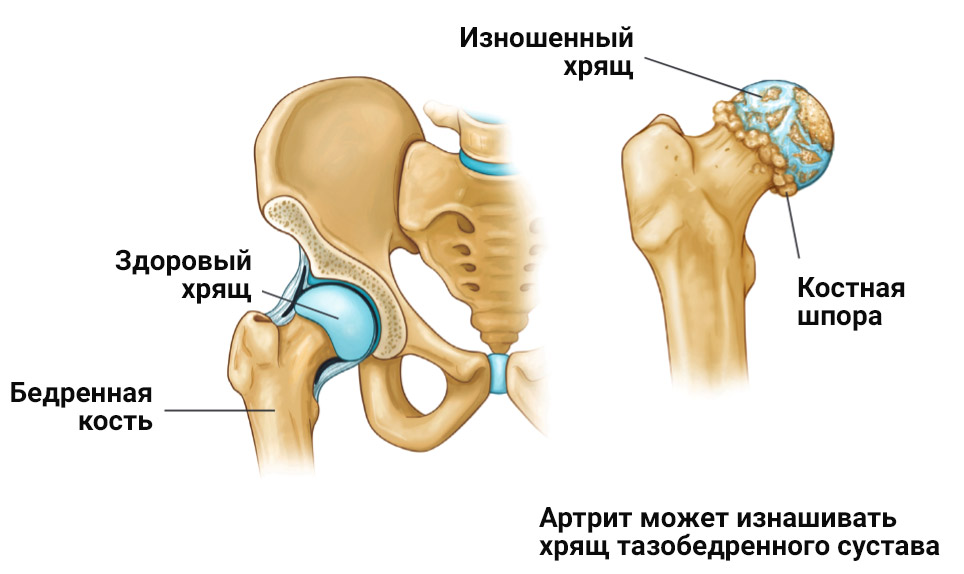

Оссификация тазобедренных суставов: что это и как проявляется?